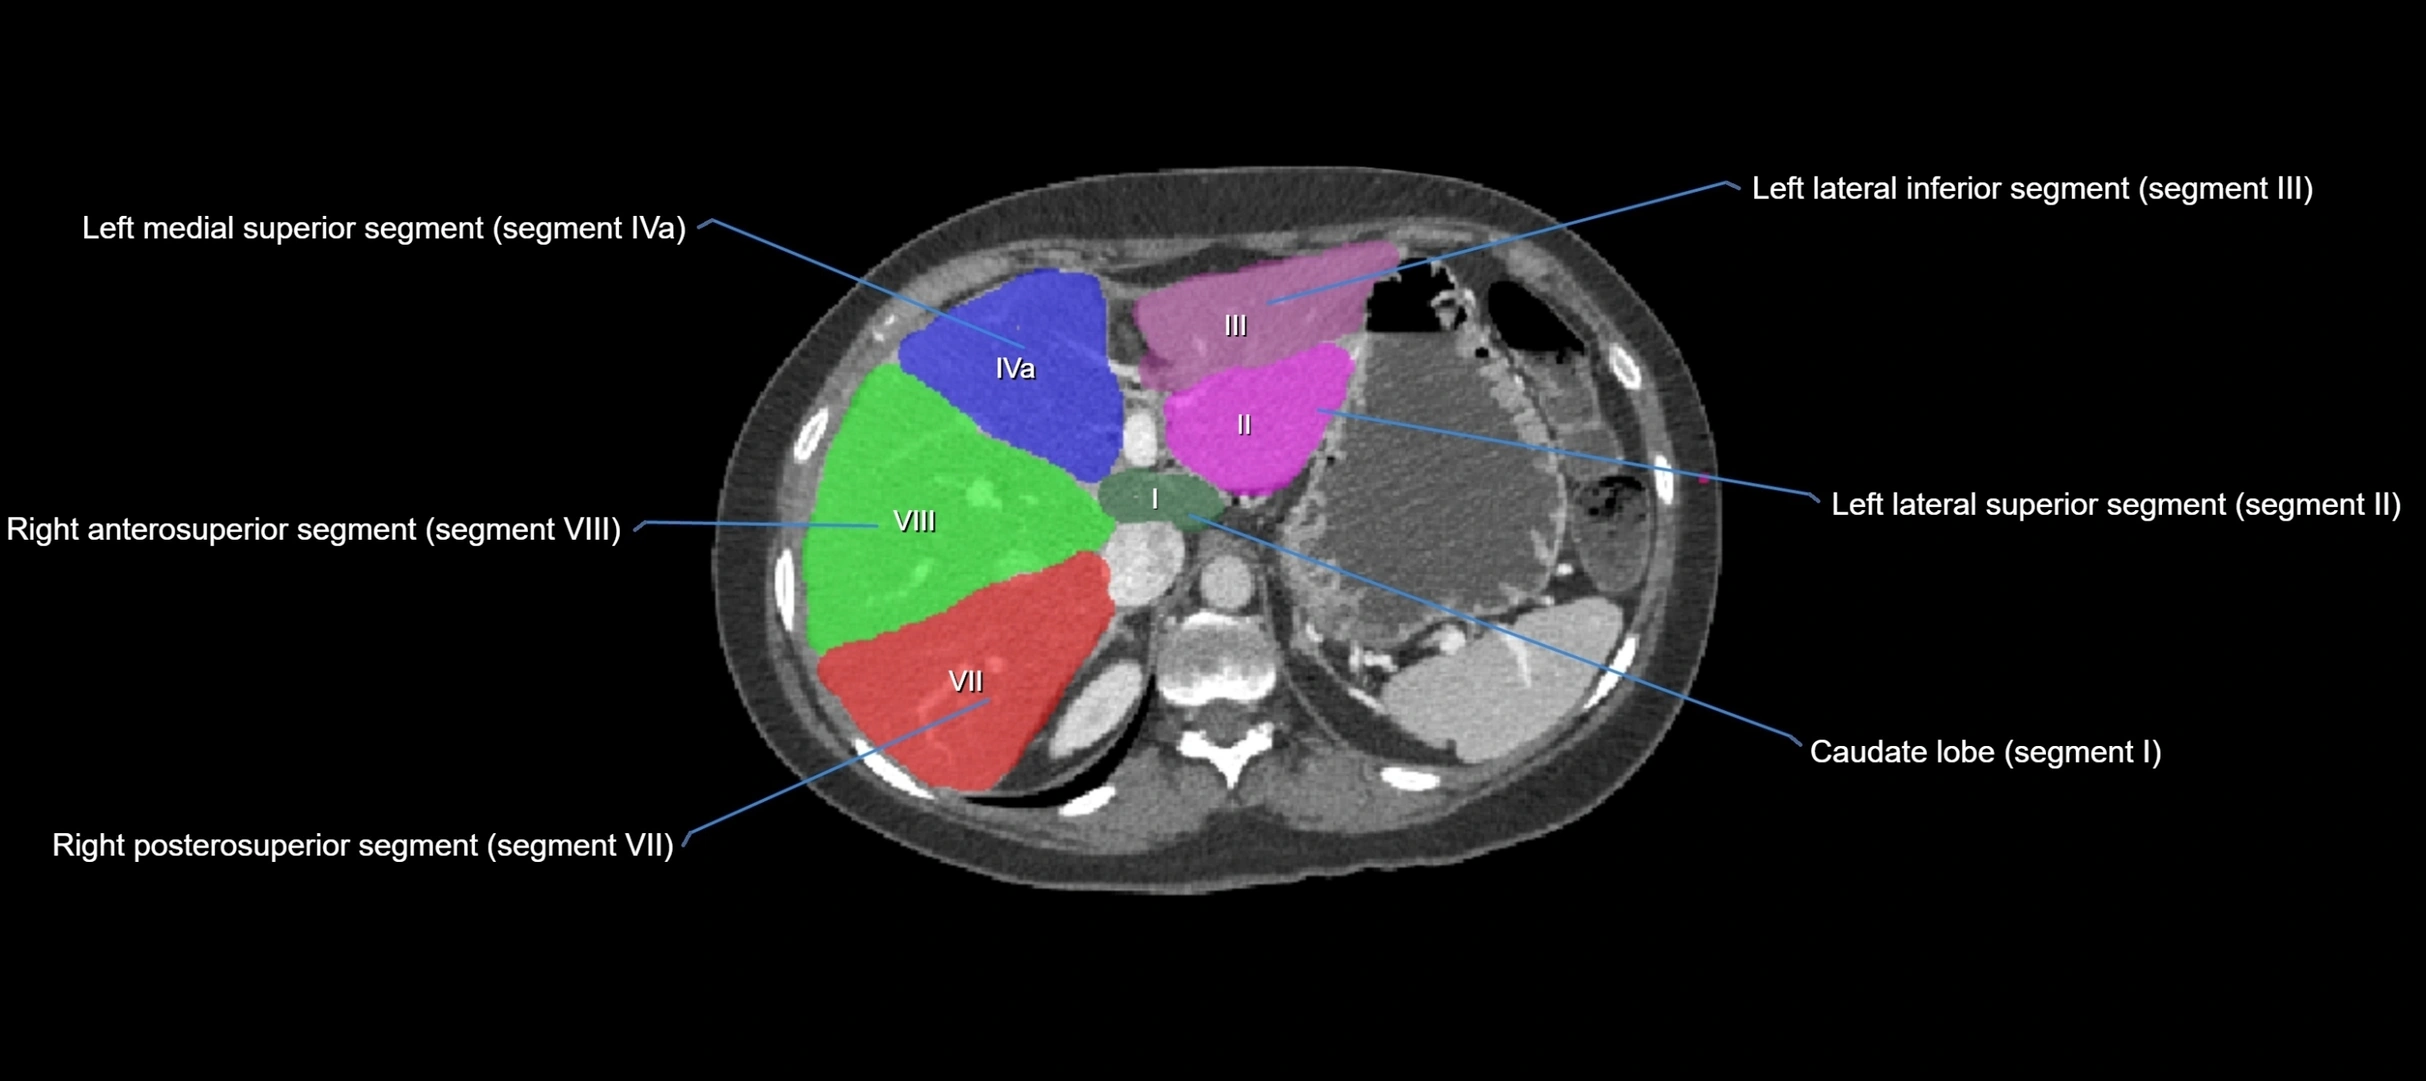

The caudate lobe of the liver is a distinct anatomical subdivision of the liver, designated as segment I in Couinaud’s classification. It lies on the posterior surface of the liver, between the fissure for the ligamentum venosum (left boundary) and the groove for the inferior vena cava (IVC) (right boundary). Superiorly, it is related to the posterior liver surface, and inferiorly it is separated from the left lobe by the porta hepatis.

CT Image

image